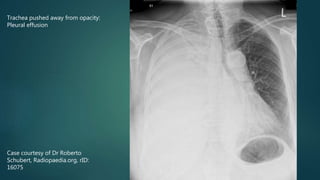

 Trachea pushed away from opacified side

 Pleural effusion

Case courtesy of Dr Roberto

Schubert, Radiopaedia.org, rID:

16075

Trachea pushed away from opacity:

Pleural effusion

Case courtesy ofDr Roberto Schubert, Radiopaedia.org, rID: 16075 Trachea pushed away from opacity: Pleural effusion